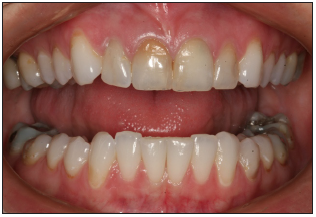

Front smile view

Show a full natural smile. Face should be relaxed. The vertical center of the slide should be the philtrum of the upper lip. Avoid compensating for midline discrepancies.

Confirm that the incisal plane of the maxillary teeth is the horizontal middle of the photo. If patient presents a canted incisal plane, duplicate position in this view. Camera should not be tilted to compensate for canted midline.

Stand directly in front of patient for straight on view. The camera should be 90 degrees to the patient's face. Teeth normally viewed in full natural smile should appear in image. Mandibular teeth may not appear.